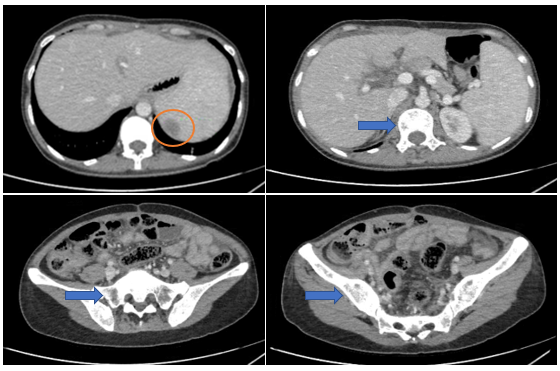

Hình 6

. Hình ảnh nốt ngấm thuốc kém ở lách (vòng tròn màu cam). Các ổ khuyết xương lan tỏa nhiều vị trí (mũi tên màu xanh) trên phim chụp cắt lớp vi tính.